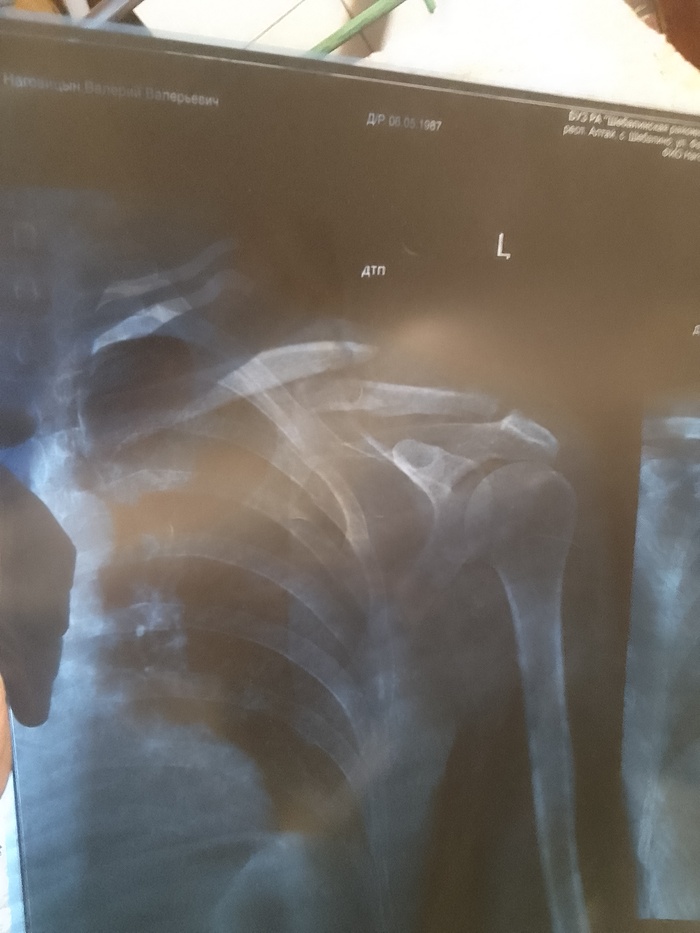

Всем привет. В общем и целом попал в дтп 24.09. (Мой апм совет не ездить на попутках). Собрали 4 встречных автомобиля,в 5-ю прилетел аккумулятор от нас.и разбил лобовое. Удар был в левый борт. Спасатели спилили крышу чтобы нас вытащить. Был за водителем слева. Сломано: шея, ключица, 3 ребра. Сотрясение мозга. 4 ушиба спинного мозга(позвоночника). Сидел я На пассажирском сиденье.был пристегнут. После аварии сделали 2 операции. 1. Вставили титановый межпозвонковый диск. 2 поставили плиту на левую ключицу из медицинской стали. Первую операцию делали через разрез на шее.по этому 1 месяц ел только детские пюре. Интервал между операциями 6 дней. Врачи сказали что Во время столкновения когда сломало шею, задело артерию. И кровью залило левое полушарие. В итоге была амнезия.сейчас все норм. Восстановился. Когла я окреп и воосстановился через 7 месяцев после дтп. Жена ушла от меня. Через 9 месяцев мы официально развелись по обоюдному согласию . С ней мы прожили без 3-х месяцев 10 лет. После развода. Прожили еще 10 дней. Она дала мне второй шанс. Но я неисправим. В итоге мы разошлись навсегда.живем сейчас по разным городам . Расстояние 3500 километров. Жизнь продолжается в новом ключе. У меня новая работа. Новая жизнь. Теперь живу один. Берегите себя и свою жизнь и цените то , что имеете. здоровье восстановилось все, кроме мозга. Алкоголь теперь под запретом. От слова совсем. Один раз попробовал . На утро 40 минут пытался вспомнить . Кто я и где я. Всем удачи в этой жизни и никогда не расстраивайтесь по пустякам. Я выжил. И я благодарен врачам за то что спасли. И жене(теперь уже бывшей) что выходила меня после аварии.

Ключица сломана.